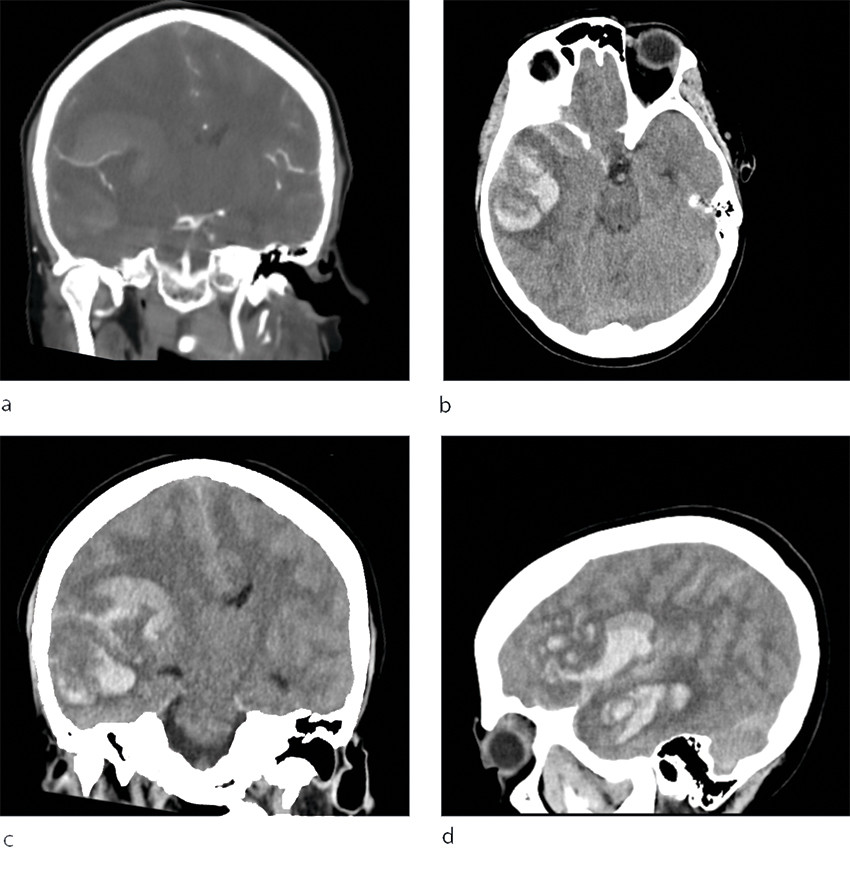

Det var sterk mistanke om intracerebral blødning, og slagalarmen ble utløst. CT caput ble rekvirert og viste en stor høyresidig intracerebral blødning temporoparietalt i forsyningsområdet til arteria cerebri media, utviklende ødem med overskyting av midtlinjestrukturer og kraftig kompresjon av høyre sideventrikkel. Det var både subaraknoidalt blod og en del ferskt blod i hjerneparenkymet (figur 1), men det var ikke synlig blod i ventrikkelsystemet. CT angiografi var uten funn av aneurisme.

Pasienten ankom universitetssykehuset tre timer etter varsling fra lokalsykehuset. Ved mottak hadde pasienten bilateral mydriasis uten lysreaksjon. Behandling med mannitol ble igangsatt, og CT caput tatt umiddelbart etter ankomst viste progrediering av en stor intrakranial blødning med startende herniering (figur 2). Cerebral angiografi (TCD) var forenlig med opphørt blodsirkulasjon i hjernen, og videre tiltak ble vurdert som uhensiktsmessige.

Få dager etter denne hendelsen ble det meldt fra Rikshospitalet om flere tilfeller av alvorlige blodpropper og blødninger hos pasienter som hadde fått identisk vaksine. Også disse pasientene hadde lave trombocyttall, og i disse tilfellene klarte man å finne en sammenheng mellom hendelsene og vaksinen (1). Tilstanden er etter dette omtalt som vaksineindusert trombotisk trombocytopeni (VITT), som kjennetegnes av lave trombocyttall, trombedannelser og antistoff mot platefaktor 4 (1, 5). I lys av denne kunnskapen ble det gjort nye undersøkelser, og man fant også hos vår pasient tendens til trombedannelse med små tromber i sinus transversus, pannelapper og a. pulmonalis. Det ble også påvist antistoff mot platefaktor 4. Samlet sett er det derfor mye som taler for at dette var et tilfelle av vaksineindusert trombotisk trombocytopeni. Retrospektivt må man spørre seg om blødningen sett på CT representerte et venøst hemoragisk infarkt tilsvarende det som ble sett hos flere pasienter på Rikshospitalet (1), og om blødningskomponenten kan ha vært dominerende som følge av vaksineindusert trombotisk trombocytopeni. Et venøst infarkt kunne kanskje forklare pasientens hodepine.